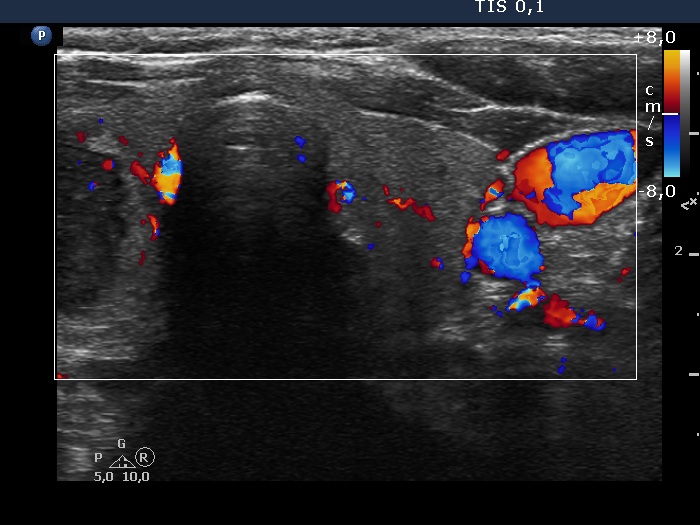

Left lobe, transverse view, color Doppler mode. The vascularization is not specific.